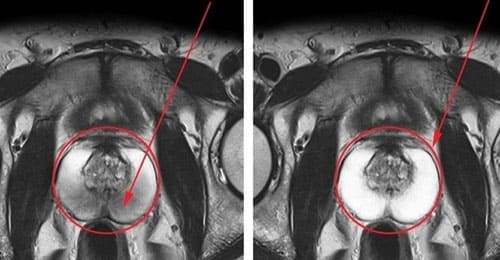

Bluestone lindert Entzündungen der Prostata

Vor Bluestone Nach Bluestone Im zweiten Stadium wirkt Bluestone wie Sildenafil (Viagra) - es beschleunigt die Stickoxidsynthese im Blut, entspannt und erweitert die Arterien. Blut füllt die schwammigen Körper des Penis und die Muskeln an der Basis des Penis, und es treten Erektionen auf - auch bei Patienten mit Erektionsstörungen. Im Gegensatz zu Sildenafil wirkt Bluestone jedoch nicht lokal auf die Gefäße des Penis (was für das Herz gefährlich ist), sondern auf das gesamte Urogenitalsystem. Und je breiter der Einflussbereich ist, desto geringer ist die Belastung des Herzmuskels. Daher kann Bluestone sowohl von Männern ab 50 Jahren als auch von Personen mit Herz-Kreislauf-Erkrankungen sicher eingenommen werden.